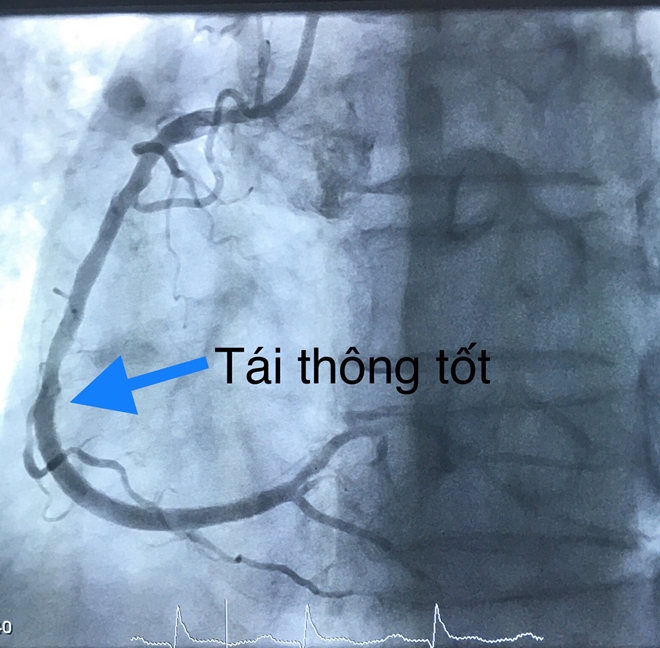

Các bác sĩ tiến hành dùng bóng nong động mạch vành phải và đặt một stent phủ thuốc. Thời gian tái thông mạch vành 20 phút.

Sau can thiệp tái thông, huyết động của bệnh nhân cải thiện rõ, sinh tồn ổn định và được đưa về Khoa Hồi sức tích cực – Chống độc để theo dõi và hồi sức nội khoa. Hiện bệnh nhân tỉnh, tiếp xúc tốt, dấu hiệu sinh tồn ổn định.

| Và sau khi được tái thông. |